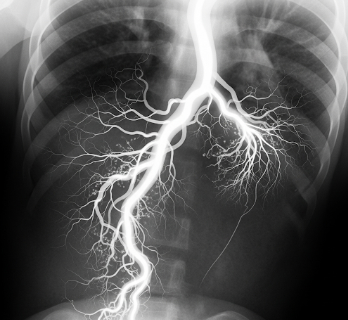

An Angiogram, also known as angiography, is a diagnostic imaging procedure used to visualize blood vessels. It helps detect blockages, narrowing, aneurysms, or other vascular abnormalities in arteries and veins throughout the body, including the heart, brain, and limbs. By providing detailed, real-time images, angiography plays a critical role in diagnosis, treatment planning, and minimally invasive interventions.

An angiogram is a minimally invasive procedure that involves injecting contrast dye into the blood vessels and capturing X-ray images to evaluate blood flow.

• Uses X-ray or fluoroscopy for imaging